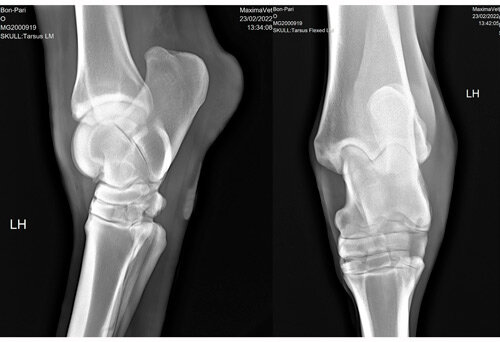

Снимки с разных ракурсов дополняют картину болезни. Важно сделать несколько снимков при диагностике сложных и ассиметричных структур, таких как крупные суставы.

На иллюстрации изображены рентгеновские снимки скакательного сустава лошади в боковой (слева) и прямой (справа) проекциях. Скакательный сустав у лошади – аналог голеностопного сустава у людей. Это сложный сустав, который состоит из множества костей и связок.